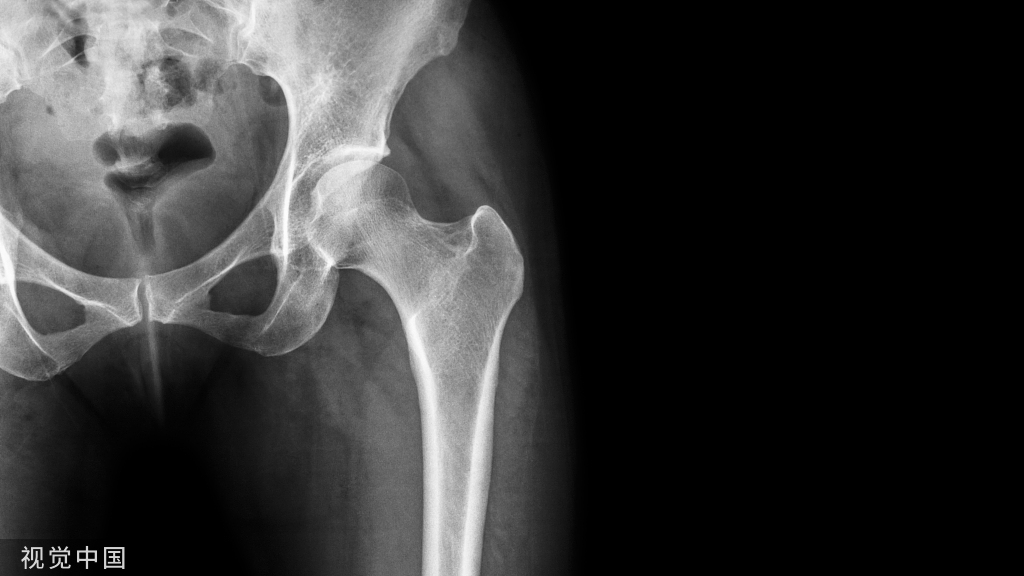

早期研究报道的骶骨衰竭骨折的发生率为1-1.8%,近期的一项研究调查了250 名到急诊科就诊并CT成像的疑似骨盆损伤患者。在被诊断患有骨盆骨折的 46 名患者中,11 名患者 (4.4%) 被发现患有骶骨衰竭骨折。多见于平均年龄 70-75 岁的患者。下图中1区为骶骨衰竭骨折常见区域。